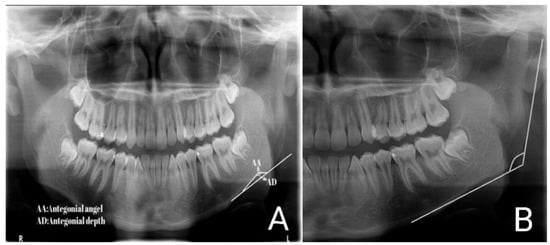

2. Materials and Methods